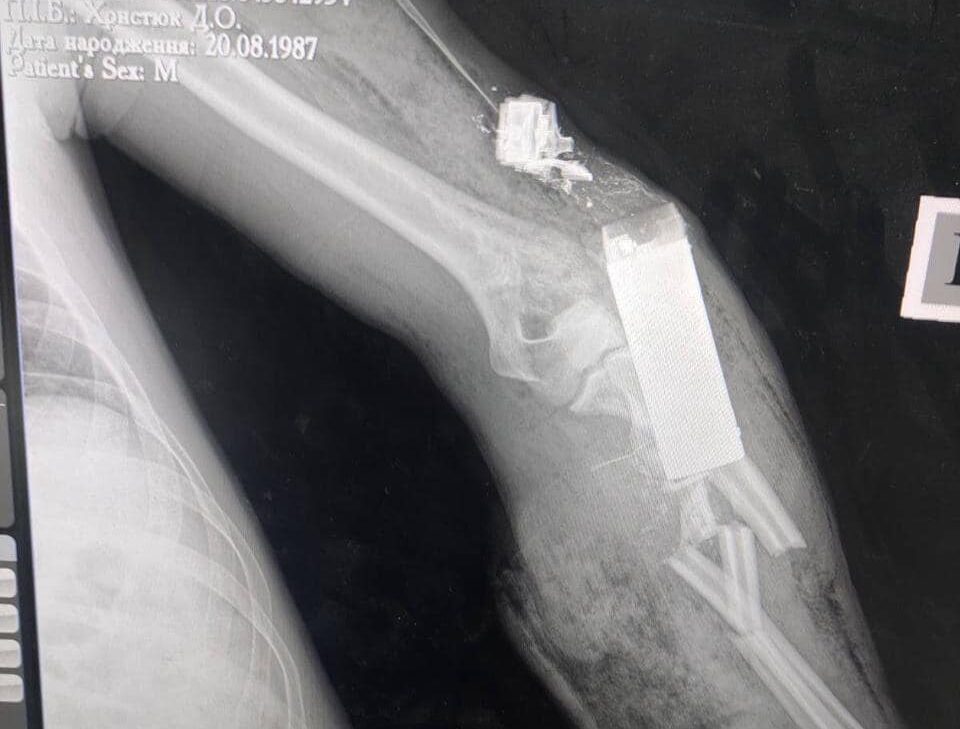

Військові лікарі провели успішну операцію і вилучили елемент бойової гранати ВОГ з тіла українського захисника. Отже, лікарям вдалося врятувати не тільки життя військового, а і його руку.

«Те, що ви бачите на фото, — бойовий елемент гранати ВОГ-17, який поцілив прямо в руку українського захисника. На щастя, наші військові лікарі дістали його з руки пораненого, врятувавши йому не тільки життя, але й кінцівку», — йдеться в повідомленні.